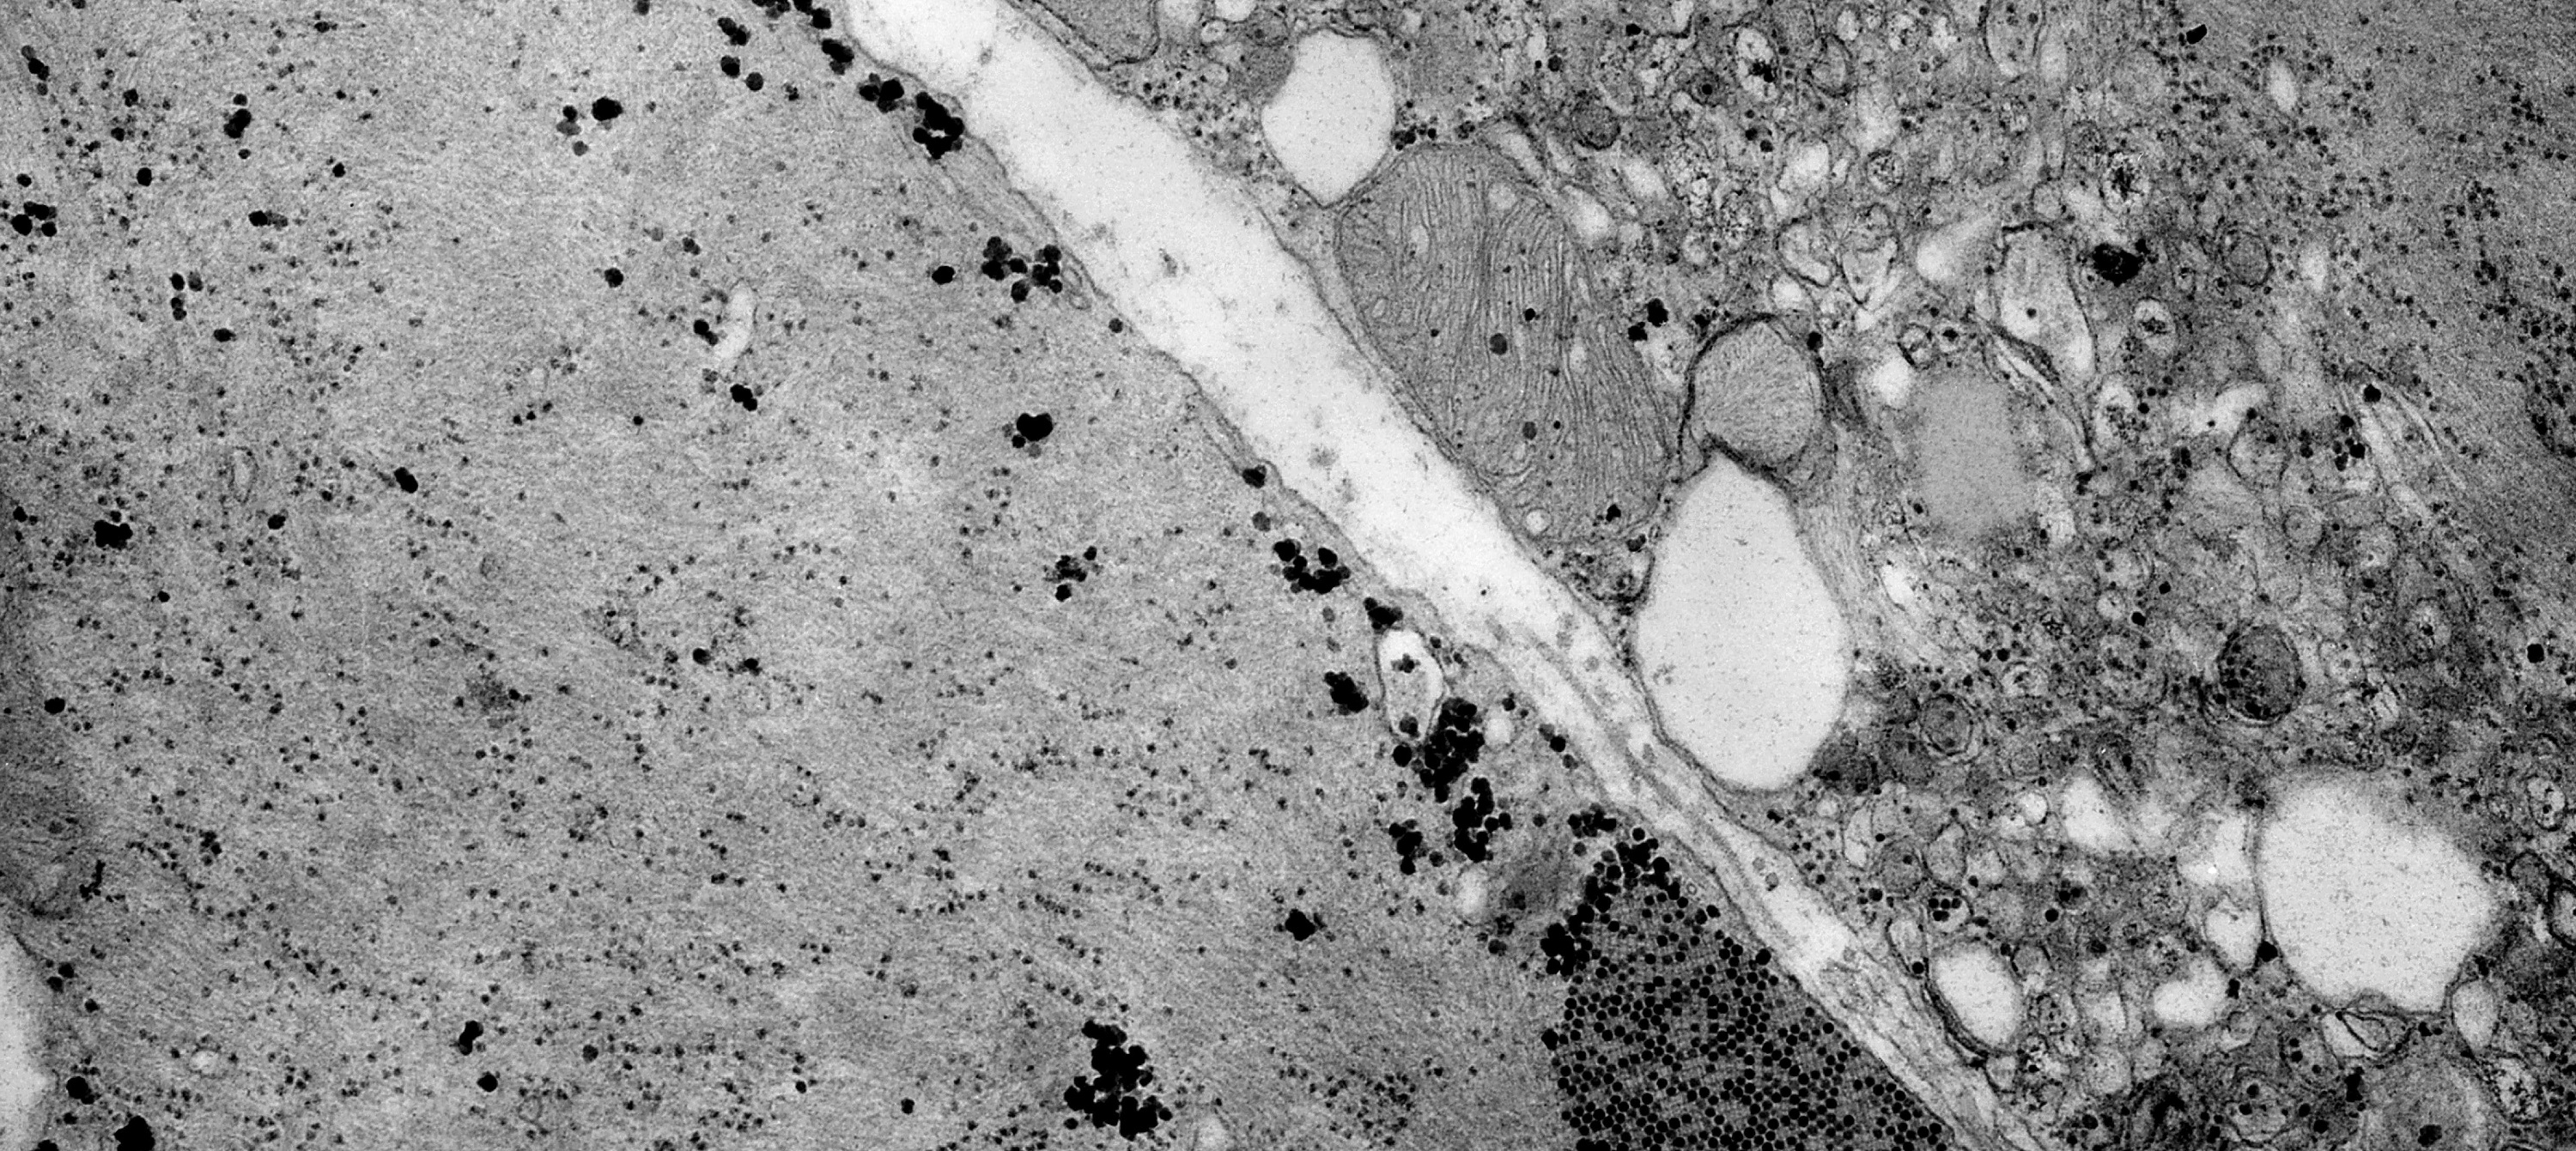

La diabetes altera la neurotransmisión de la dopamina y aumenta la vulnerabilidad al daño neurodegenerativo